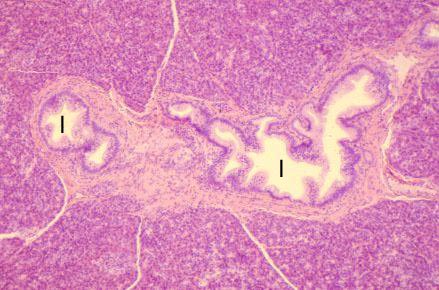

VIII-24, Slide 68, Pancreas (H&E). Large interlobular ducts (I) are present in a connective tissue septum.